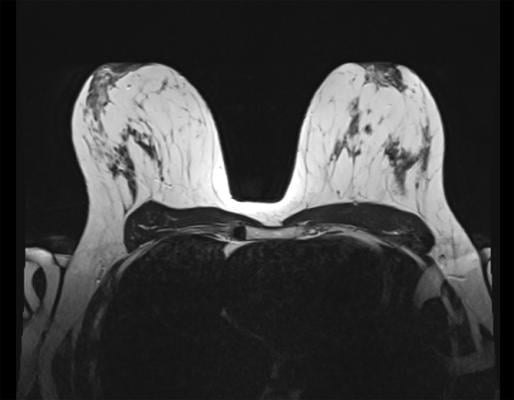

February 1, 2023 — Compared to other common supplemental screening methods, breast MRI was superior at detecting breast cancer in women with dense breasts, according to a study published in Radiology, a journal of the Radiological Society of North America (RSNA).

Supplemental screening may be required to assist in cancer detection in women with dense breasts. The four most common supplemental imaging tests are hand-held breast ultrasound, automated breast ultrasound, digital breast tomosynthesis and breast MRI.

Meta-analysis showed that of the 132,166 patients with dense breasts, a total of 541 breast cancers that were initially missed on mammography were detected with supplemental screening methods. Breast MRI was the superior screening method and was capable of detecting even the smallest of cancers. Excluding MRI, there was not a significant difference between the other supplemental screening methods.

“MRI is far superior in terms of cancer detection compared to hand-held ultrasound, automated ultrasound and digital breast tomosynthesis,” Dr. Freitas said. “Our results about the role of MRI in supplementary screening will allow stakeholders to guide healthcare policies in this setting and direct further research.”